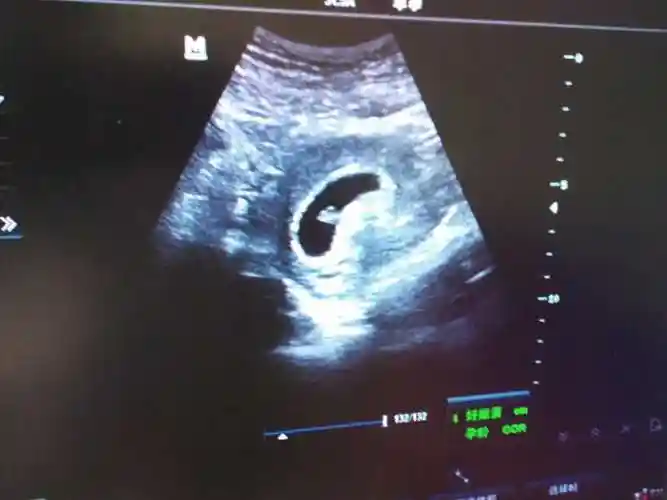

六周的孕囊能看出怀几个孩子吗孕早期通过孕囊形状看男女不靠谱

孕囊形状为圆形就代表一定是生女孩吗

孕囊的形状一般是呈椭圆形或者是月亮型.

民间有传闻说长孕囊生男孩,圆孕囊生女孩,但实际上这种说法并不准确